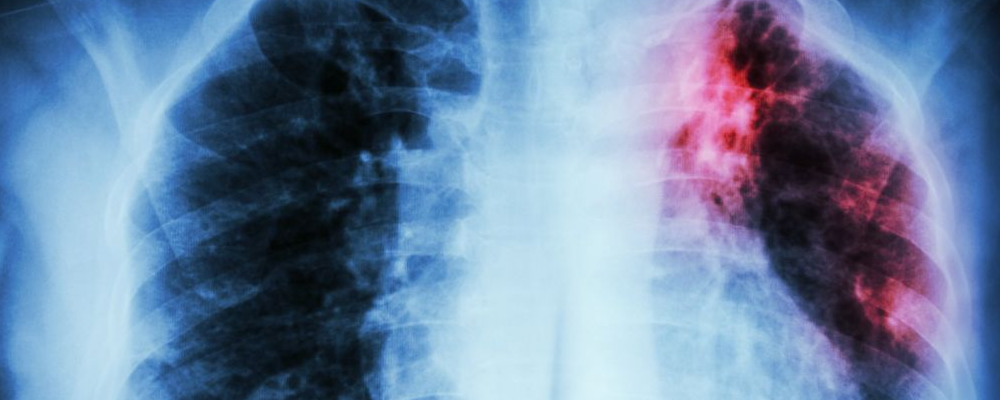

肺癌是一种恶性肿瘤,它发生在肺组织中。肺是我们呼吸系统的关键器官,负责吸入氧气并将其输送到全身。然而,肺癌是全球范围内最常见的癌症之一,它对人类的健康造成了巨大的威胁。

肺癌的症状常常在晚期才显现,这使得早期诊断和治疗变得更加困难。一些常见的症状包括持续性咳嗽、咳血、胸痛、呼吸困难、声音嘶哑、体重下降和疲劳。如果出现这些症状,特别是在吸烟史或家族病史存在的情况下,应尽快寻求医疗建议。